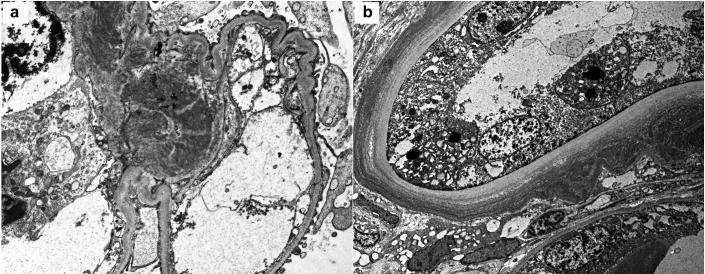

α1-Heavy Chain Deposition Disease With Negative Immunofluorescence Staining on Renal Biopsy.

Kidney Int Rep. 2018 Sep 18;4(1):178-183. doi: 10.1016/j.ekir.2018.09.007. eCollection 2019 Jan.

DOI:10.1016/j.ekir.2018.09.007

PMID:30596184